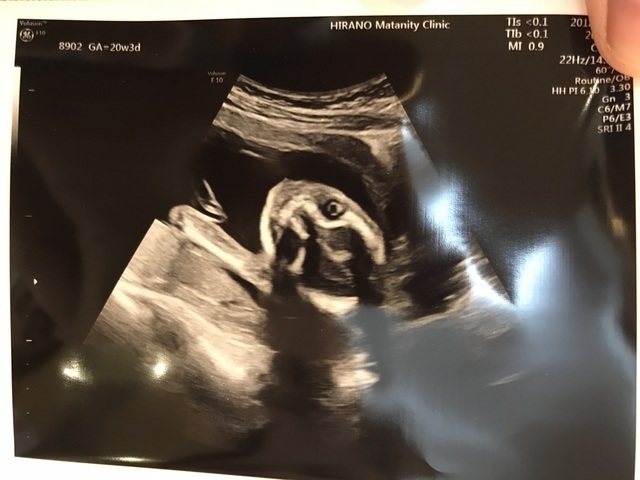

24週2日(24w2d・男の子)|McHiro さん(34歳)

エコー写真撮影時のエピソード:

妊婦健診のエコーでなかなか顔を見せてくれないのですが、今のところ唯一顔がうつったので、うれしくて家族に送付した、思い出の一枚です。

出産予定場所が3Dや4Dエコーは扱っていないので、目はうつりませんでしたが、鼻や口が見れただけでも、胎内で着実に大きくなっていっているのを実感し、益々会えるのが楽しみになりました。

妊娠のマイナートラブルや職場で辛い時は、エコー写真を見ると頑張ろうと思えます。